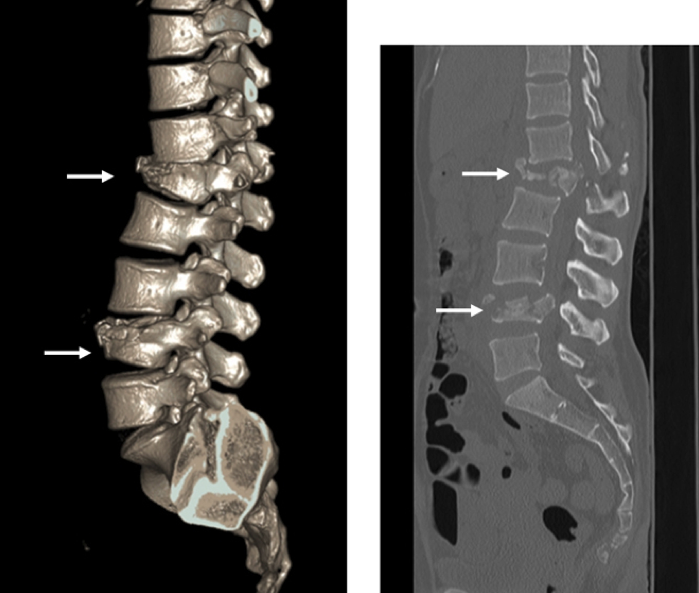

腰椎椎間板ヘルニア